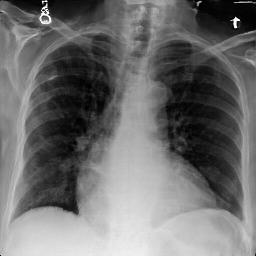

Fig. 3: Anonymization results. Real images XRX_{R} randomly selected from the training, validation, and test sets are displayed in the first column. The corresponding reconstructed images X^R\hat{X}_{R} are displayed in the second column. The anonymized images XAX_{A} are displayed in the last three columns.

Qualitative Results The visualization results are shown in Fig. 3. In this figure, the anonymized images optimized using only the utility loss ut\mathcal{L}_{ut} (column 3) exhibit greater visual similarity to their real counterparts (column 1), while those optimized using only the identity loss id\mathcal{L}_{id} (column 4) appear more distinct from their originals. Additionally, the anonymized images optimized with both the ut\mathcal{L}_{ut} and the id\mathcal{L}_{id} (column 5) strike a balance, appearing more realistic by simultaneously considering both identity removal and utility preservation.